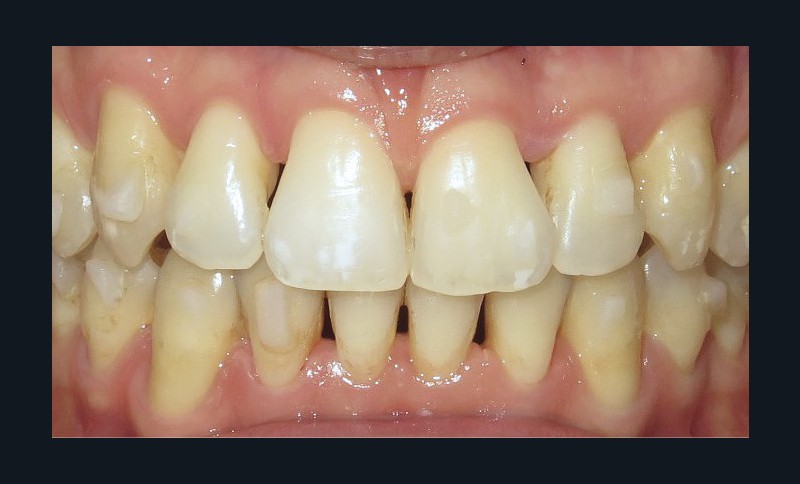

Le patient consulte initialement pour des défauts d’alignement. L’examen clinique confirme l’existence d’un encombrement antérieur bimaxillaire, mais révèle aussi la présence d’une Classe II dentaire sévère, d’une exoclusion de la 27 et de troubles parodontaux (peu ou absence de papilles inter-dentaires). Sur le plan squelettique, le patient est relativement équilibré avec un profil harmonieux.

Discussion (fig. 5a- i)

La difficulté a été de garder le patient motivé, car les trois temps du traitement se sont ajoutés (2,5 ans) et le traitement reposait beaucoup sur sa coopération (dispositifs amovibles à savoir les élastiques et les gouttières).

Cependant, le patient est récompensé des choix qui ont été faits, car désormais son sourire est harmonieux avec une occlusion équilibrée. L’augmentation des triangles noirs a été limitée grâce aux soustractions amélaires au niveau des faces proximales des dents antérieures. En revanche, pour parfaire le résultat au niveau esthétique, des apports de composites ont été réalisés, car les dents de devant étaient très pincées au niveau cervical.

Le traitement est stable dans le temps, car les contacts occlusaux sont harmonieux ainsi que les fonctions et les déplacements ont été surtout coronaires.